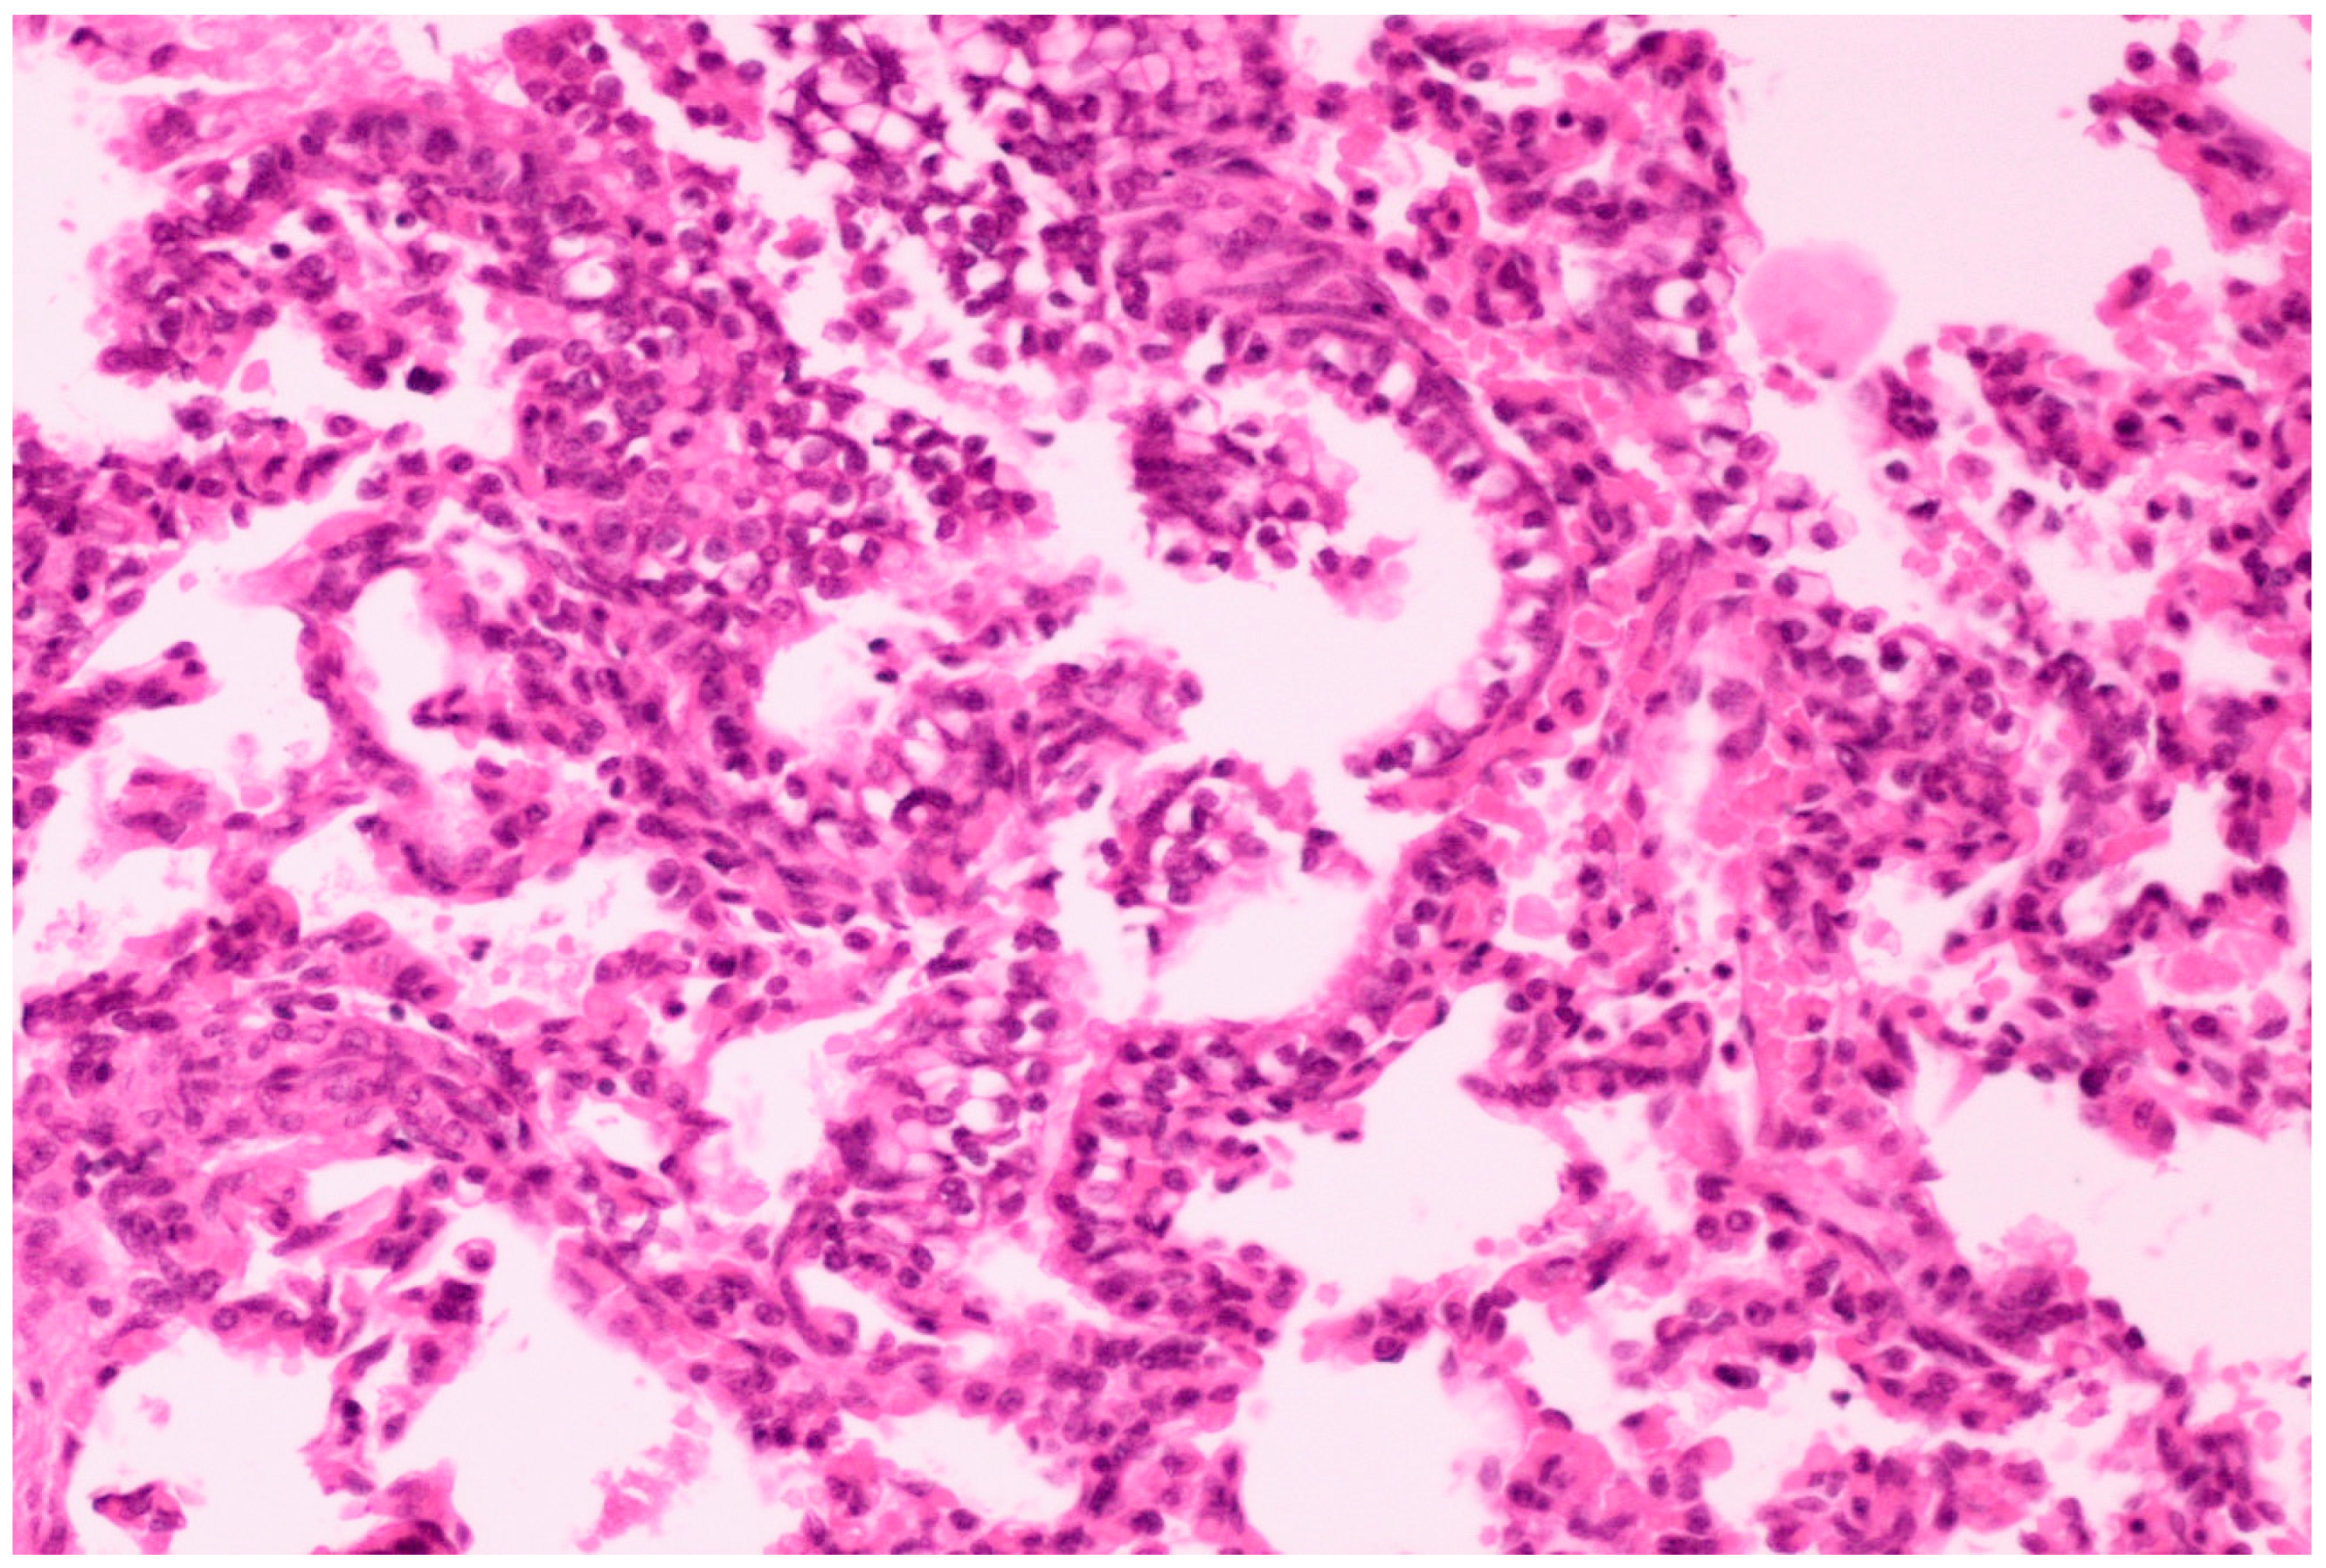

3.3.2. Histopathological Lesions

3.3.3. Scanning Electron Microscopy (SEM) Findings